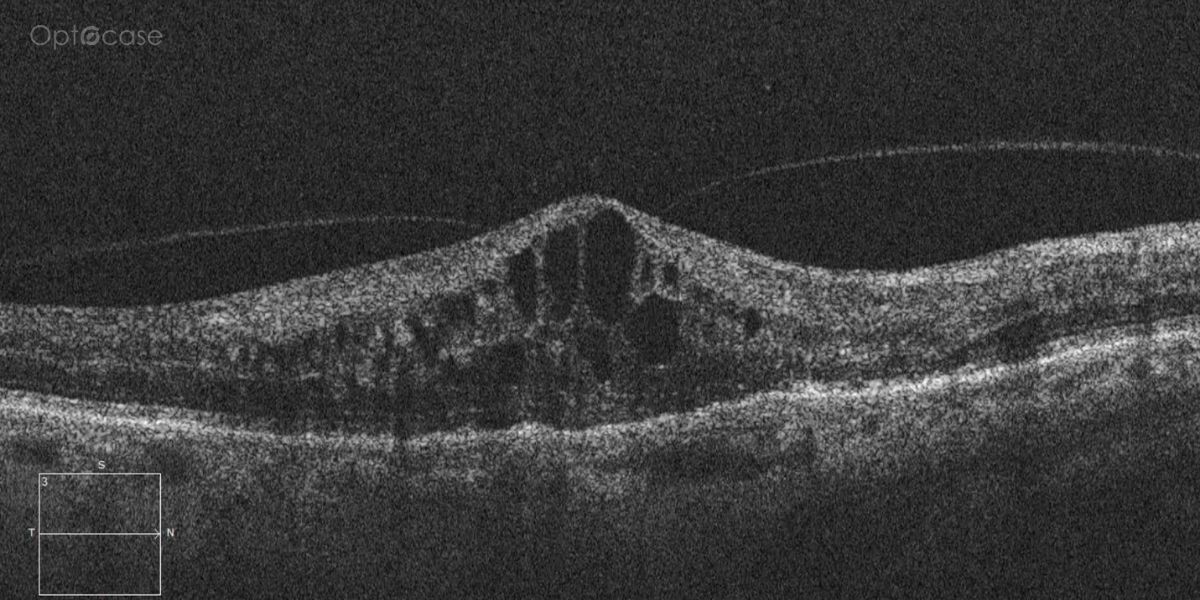

Here there is loss of the regular macular depression. There is a bright line present on the surface of the retina. In addition, there is separation of the retinal layers in the inner retina.

The patient was diagnosed with a schisis secondary to an epiretinal membrane. This complication is seen in over 50% of ERMs (video).

In any patient with intraretinal fluid consider the possibility of an epiretinal membrane causing a schisis.